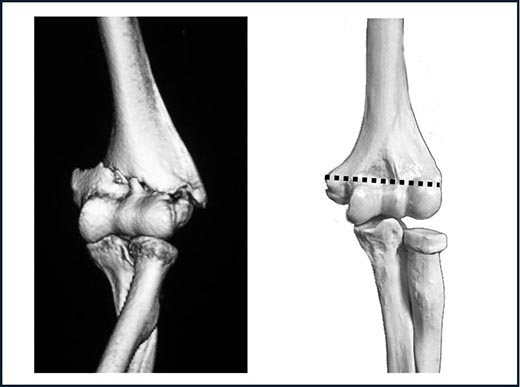

- 上腕骨通顆骨折(〜つうかこっせつ)

上腕骨内側上顆と上腕骨外側上顆を通る直線状の横骨折です(図2)。高齢の方に多く、転倒のような比較的小さな力で発生します。小児期に骨が成長していた部位(骨端線)に一致した骨折のため、骨折面が平面状で凹凸が少ないことから不安定な骨折です。そのため、初めは転位(ズレ)していない骨折であってもギプスで固定している間に転位が生じ、骨がつかないままになってしまうことがあります。

図2.上腕骨通顆骨折:上腕骨内側上顆と外側上顆を通る横骨折です。